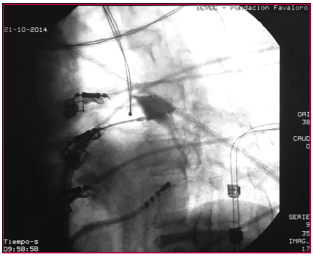

Introducción: El aislamiento eléctrico de las venas pulmonares constituye la piedra angular en el tratamiento curativo de pacientes con fibrilación auricular paroxística (FAP) recurrente y sintomática. La crioablación con balón (CAB) es una alternativa a la radiofrecuencia, con disminución de los tiempos del procedimiento y de radioscopia.

Material y métodos: Entre noviembre de 2013 y febrero de 2015, 23 pacientes fueron intervenidos con una CAB de FAP. Previo al procedimiento se les realizó una angiotomografía con reconstrucción de la aurícula izquierda y las venas pulmonares.

Resultados: La edad promedio de los pacientes fue de 53 ± 11 años, 19 eran varones, el diámetro de la aurícula izquierda fue de 40 ± 7 mm, la FEVI fue de 58% ± 8%. El CHA2DS2VASc promedio fue de 0,6. La duración promedio de los procedimientos fue de 169 ± 47 minutos, con un tiempo de radioscopia de 39 ± 17 minutos. Se logró el aislamiento en 89/91 venas pulmonares (97,8%); en 2 pacientes se debió completar la lesión con radiofrecuencia. Un paciente (4,34%) presentó parálisis diafragmática transitoria, con recuperación espontánea a los 30 minutos. No hubo otras complicaciones. Con una mediana de seguimiento de 9,2 meses, 21 pacientes (91,3%) permanecieron en ritmo sinusal.